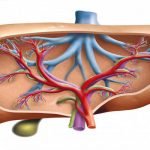

الكبد واحد من أهم الأعضاء والغدد الموجودة في جسم الإنسان وهو يقوم بعمل الكثير من الوظائف الحيوية التي لا يمكن الاستغناء عنها ووجود أي مشكلة أو عدوى في الكبد يؤدي إلى مخاطر جسيمة تهدد حياة الإنسان، أما أهم وظائف الكبد فهي كالتالي:-

- مسئول عن العديد من الوظائف الحيوية المهمة في جسم، ويصل عدد هذه الوظائف إلى ما يقرب من 500 وظيفة وأي خلل فيها يعمل على وجود مشكلات صحية كبيرة.

- الكبد يقوم بإفراز مجموعة كبيرة ومهمة من الهرمونات التي تتحكم في العديد من الوظائف في الجسم.

- من أهم الأدوار الحيوية التي يقوم بها الكبد هي القيام بتنظيف الجسم من السموم والمواد الخطرة وأهمها الأمونيا.

- يعمل الكبد على إنتاج جزء كبير من البروتين الذي يحتاجه الجسم كما أنه يعمل أيضاً على إنتاج الدهون الثلاثية والكربوهيدرات وعوامل تخثر الدم.

- يقوم الكبد بإنتاج الصفراء وهي واحدة من أهم المواد التي تساعد في عملية هضم الطعام.

- الكبد يعتبر جزء لا يتجزأ من الجهاز المناعي وذلك لأنه يقاوم العديد من الأسباب التي تؤدي إلى الإصابة بالأمراض المختلفة.